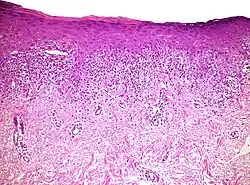

Spongiotic dermatitis

It is characterized by epithelial intercellular edema.[2]

| Generally/Not otherwise specified[notes 2] | Typical findings:[2]

Typical findings:[2]

PAS stain is essential to exclude fungal infection.[2] |